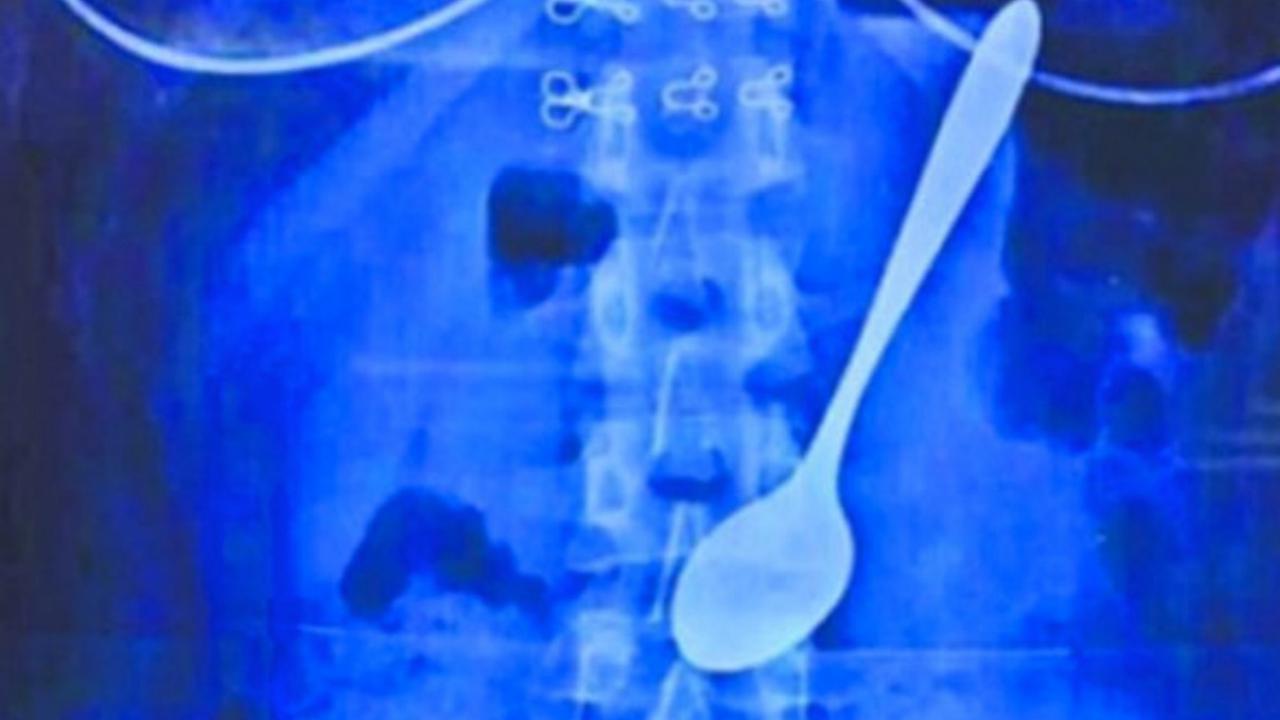

Liputan6.com, Jakarta Sendok sepanjang 14 sentimeter terperangkap di dalam tubuh seorang mahasiswa asal Provinsi Wuhan, China bernama Hubei (22).

Dikutip dari situs South China Morning Post, Senin (22/6/2015), pada akhirnya Hubei memutuskan ke dokter dan melakukan rontgen. Karena keberadaan sendok tidak terlalu dalam, diputuskan pengambilan sendok tidak perlu melalui jalan operasi. Cukup menggunakan alat semacam pancingan ikan untuk menarik sendok dari perutnya.

Prosedur ini tak memakan waktu lama, hanya 10 menit, dan tidak menimbulkan pendarahan internal.